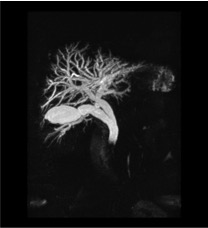

JUSTIFICACIÓN: es la técnica de elección para el diagnóstico de la patología de la vía biliar pues entre sus ventajas encontramos que no irradia al paciente y nos aporta una imagen de toda la vía biliar muy explícita. Permite estudiar órganos y sistemas con fluidos en movimiento sin requerimiento de contraste. Sus desventajas serían el elevado coste y el no estar disponible en todos los centros, sin posibilidad terapéutica.

Es visible una obstrucción del conducto colédoco que conlleva la dilatación de los conductos cístico y hepático común.

RESUMEN DEL CASO: Se realiza colangio-RMN con secuencias habituales. Apreciamos una litiasis obstructiva de 13 mm en colédoco distal que condiciona dilatación del mismo de hasta 14 mm, y también del conducto cístico, hepático común y radicales biliares intrahepáticos derechos e izquierdos. Conducto de Wirsung no dilatado.

Se trata de una litiasis obstructiva en colédoco distal que condiciona la dilatación del mismo y también del conducto cístico, hepático común y radicales biliares intrahepáticos derechos e izquierdos. No observamos el conducto de Wirsung dilatado.

Esta litiasis es conocida en la ColangioRM como “patas de cangrejo”, signo patognomónico de litiasis, debido a la presencia de un cálculo